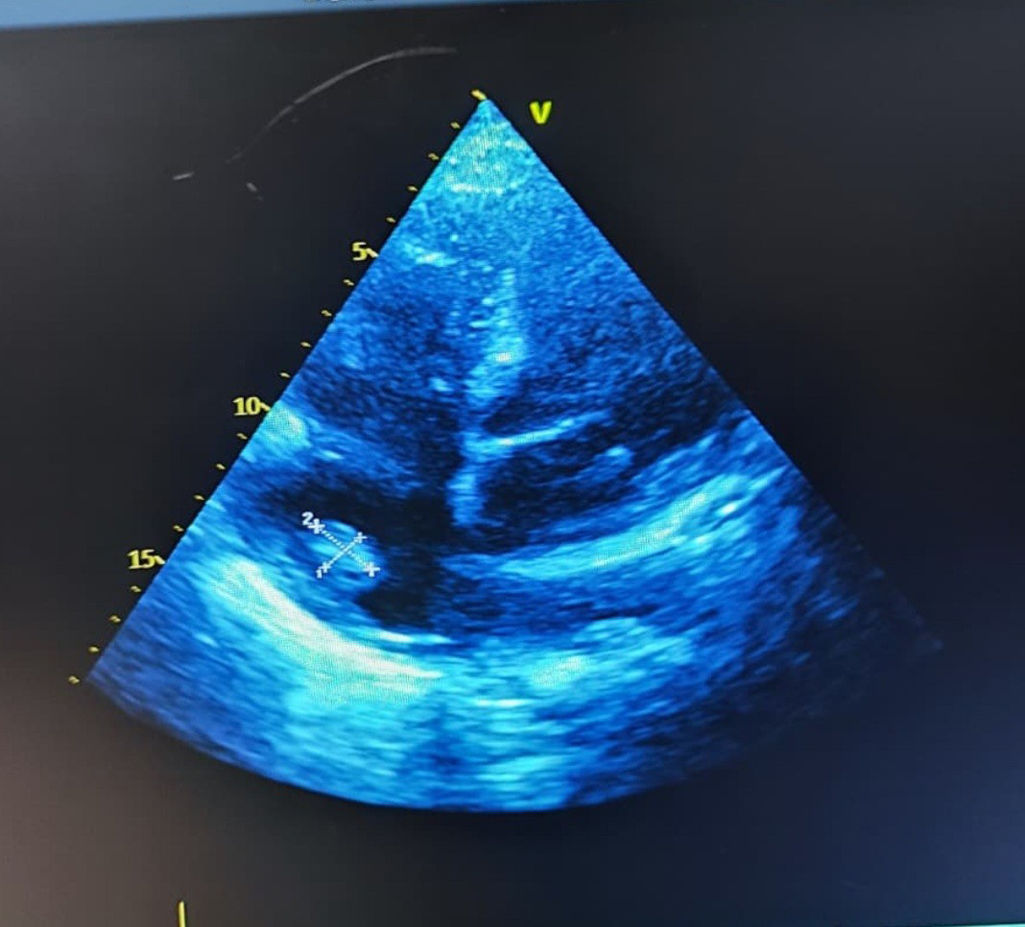

Los hemocultivos de control persistieron positivos para S. aureus en dos tomas posteriores, negativizándose en los controles subsiguientes tras el ajuste del tratamiento antibiótico. Luego de tres semanas de terapia dirigida, el ecocardiograma transtorácico de control mostró persistencia de la imagen nodular adherida a la válvula de Eustaquio, con dimensiones similares a las previamente informadas, sin evidencia de incremento en su tamaño ni de complicaciones adicionales (fig. 2). La paciente completó el esquema de antibióticos endovenosos prolongados, con mejoría progresiva de la disnea y estabilización de los parámetros inflamatorios, motivo por el cual fue dada de alta con tratamiento antibiótico oral para completar tres semanas adicionales con trimetoprim/sulfametoxazol. No se realizó ecocardiografía transesofágica debido a que el ecocardiograma transtorácico ofrecía una ventana acústica adecuada y permitía una visualización satisfactoria de las estructuras implicadas, por lo que se consideró suficiente para el seguimiento.